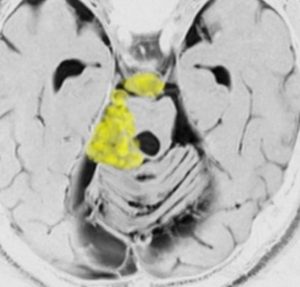

脳幹部に食い込んでいる類表皮のう胞をどうするか

とても若い患者さんで歩行障害などの脳幹部症状は全くありませんでした。第4脳室に発生して脳幹部(橋)背側に食い込んでいる類表皮のう胞です。これを全摘出することは難しく,行えば重い脳幹部症状を出す大きなリスクがあります。

患者さんとよくよく相談して,開頭手術で全摘出しました。

薄いのう胞壁を脳幹内部から確実に摘出するためには,橋の背側の脳組織をほじくり回すような手術になります。

術後は体幹失調で術直後は車椅子になりましたが,リハビリで普通に歩行ができるようになりました。眼球運動障害も回復しています。

安易にお勧めできる手術ではありませんでした。